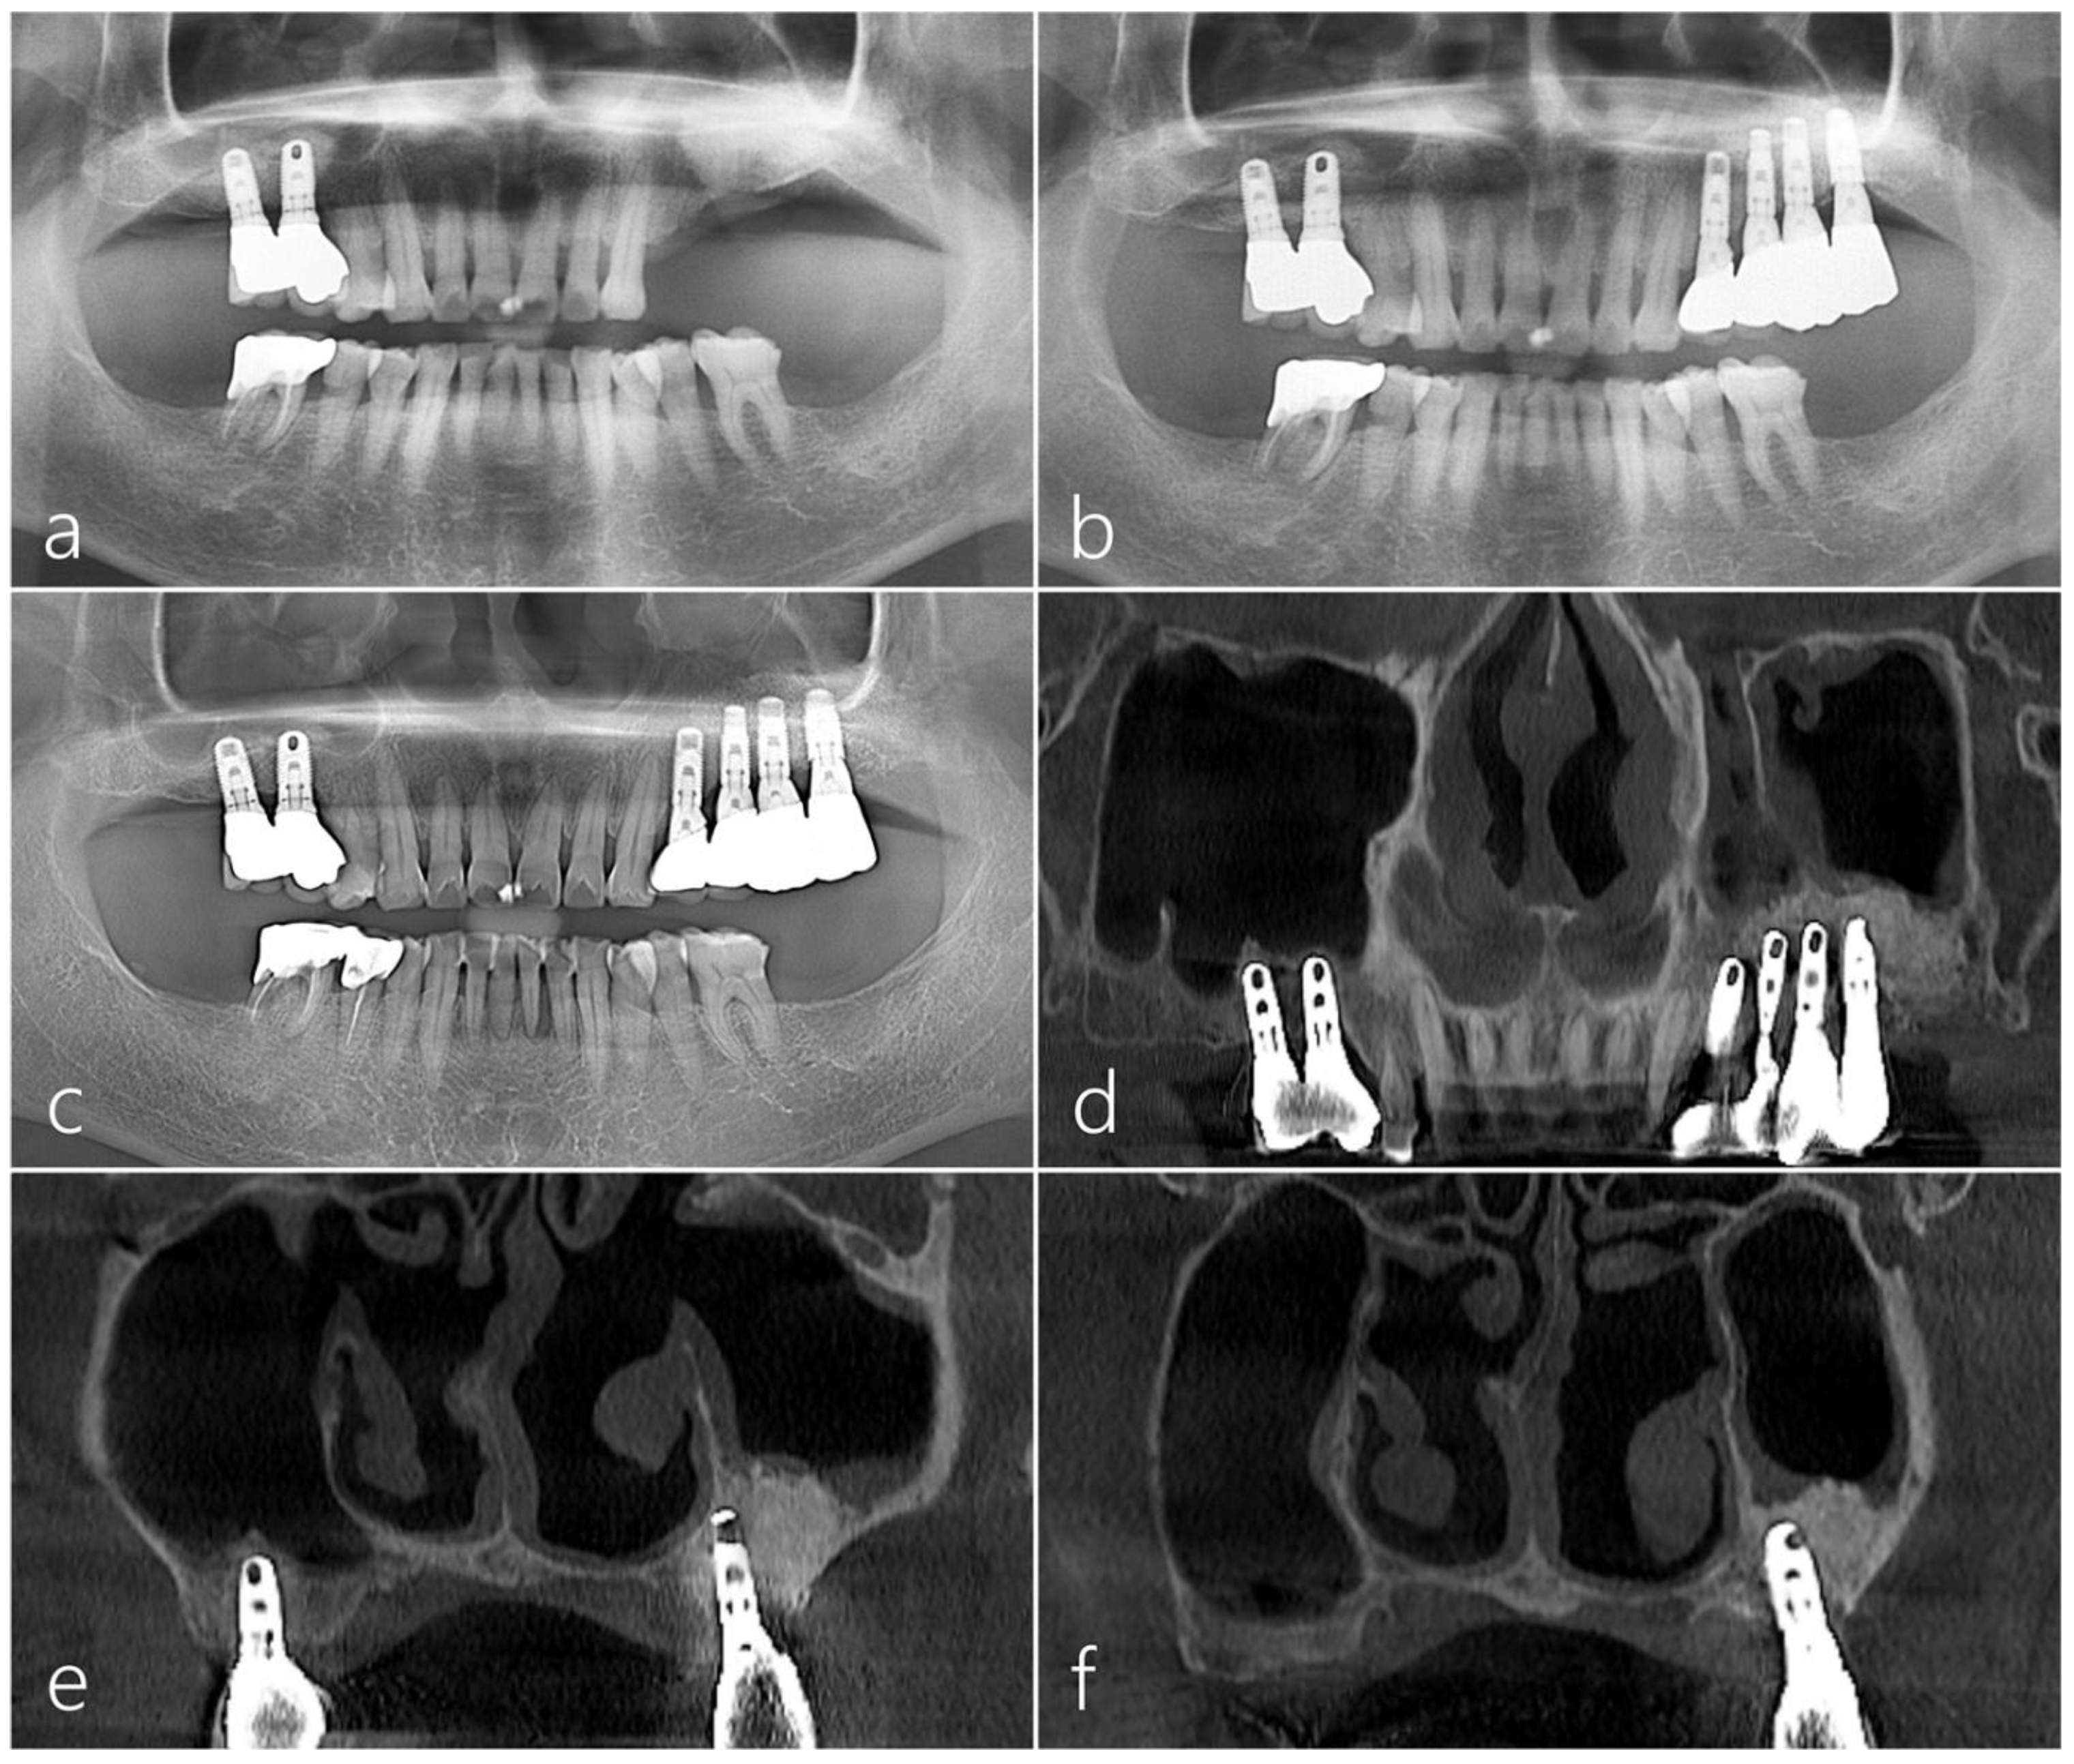

2.3. Case 3